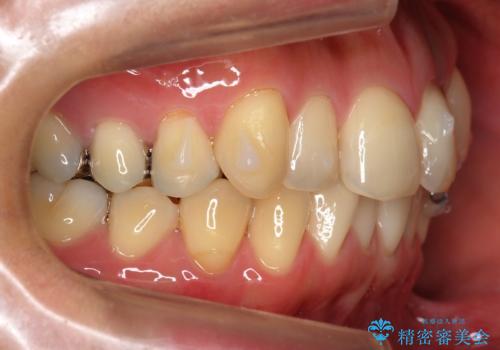

- インビザライン および ワイヤーによる部分矯正

引っ張り出すことはマウスピース矯正では難しい為、埋まっている歯を並べるスペース確保と、引っ張り出すのに、ワイヤーを用いた部分矯正を行なっています。

埋まっていた歯をしっかり引っ張り出すことができ、また、前歯の見た目も非常に良くなりました。

ワイヤー矯正を奥歯の部分的に行なっただけで、治療の大半をマウスピース矯正で行うことができ、非常に喜んでいただきました。